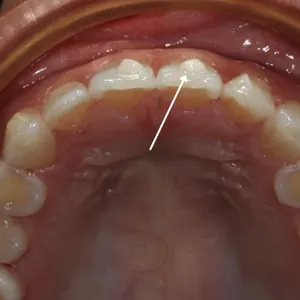

Understanding Phase 1 & Phase 2 Orthodontic Treatment

Children aged 4–10 are in mixed dentition (a mix of baby and permanent teeth). Treatments at this stage are called Phase 1, focusing mainly on skeletal development with secondary attention to teeth alignment.

Once all permanent teeth have erupted (around age 11–13), Phase 2 treatment begins, focusing fully on teeth alignment.

Skipping Phase 1 may result in longer, more invasive treatment in Phase 2 with less ideal results.